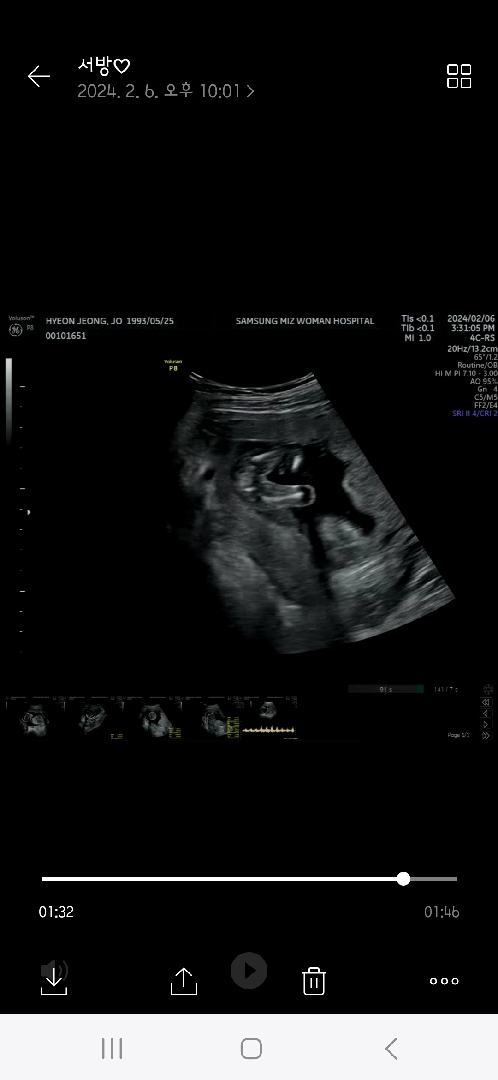

첫찌는 두돌된 아들이있어요^^ 시댁 가기전에 성별을 알아봤는데ㅎㅎㅎㅎ 15주 4일차에 다리사이 찍은 사진인데ㅎㅎㅎ 딸같나요?!ㅎㅎㅎ

정확한 16주가 아니라서ㅜㅜ반전있으까 ㅋㅋ 두근거려여ㅎ